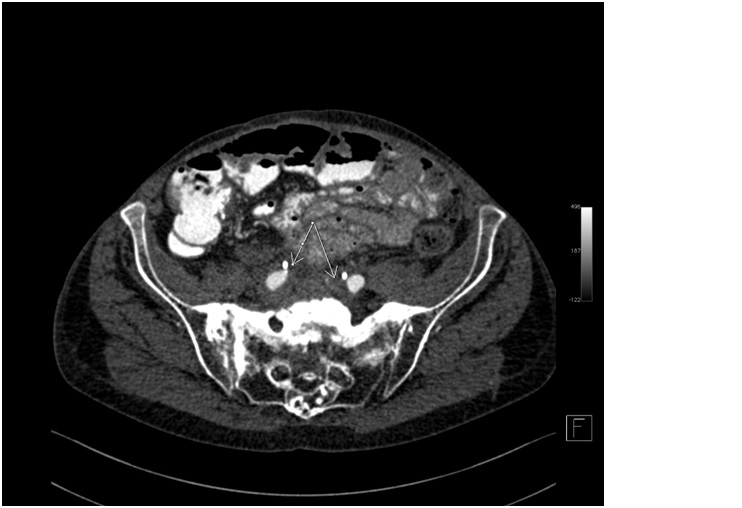

Idiopathic retroperitoneal fibrosis, or Ormond’s disease, is a rare syndrome which is in essence the deposition of pathological fibrous tissue in the retroperitoneal space. In most cases, it is initially asymptomatic, but as the disease progresses, clinical symptoms develop. The main complaint are abdominal pain and symptoms resulting from the involvement of ureters, arterial and venous vessels. Diagnosis is based on computed tomography or magnetic resonance imaging, demonstrating a fibrotic tissue mass accumulated in the retroperitoneal space. Due to the typically late presentation of clinical symptoms, a diagnosis is difficult and is often made after complications occur. In our article, we present the case of a 71-year-old patient in whom coexisting ankylosing spondylitis and retroperitoneal fibrosis were diagnosed 15 years after non-specific abdominal pain occurred.